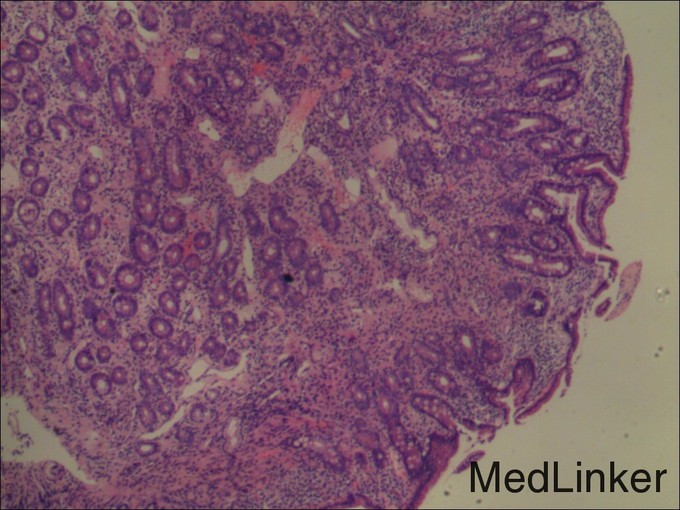

查体: 面色稍苍白,皮肤黏膜及巩膜无黄染,浅表淋巴结未及肿大,无肝掌及蜘蛛痣,无浅表静脉曲张,右上腹肋缘下处可触及一约5cm*5cm包块,界清,质软。 辅查: 电子胃镜:十二指肠降段溃疡未排恶变,病理诊断(十二指肠降段)粘膜组织呈慢炎性 腹部CT平扫+增强:胰头部肿块,考虑囊腺瘤可能性大。

诊断:1.急性上消化道出血,2.胰头占位性病变3.十二指肠降部溃疡 治疗:完善术前检查,在全麻下行“根治性胰十二指肠切除术”,术程顺利,术后病理提示:十二指肠间质瘤,高危险度;出院后休息两周予格列卫口服化疗。

患者慢性贫血与消化道长期失血有关,当地仅凭一次胃镜活检未提示恶性病变,便只以良性病变诊治,应该说不全面。对于向腹腔外生性生长的肿瘤,内镜很多时候取不到合适的标本,此时需借助增强CT等影像学评估肿瘤生长情况。